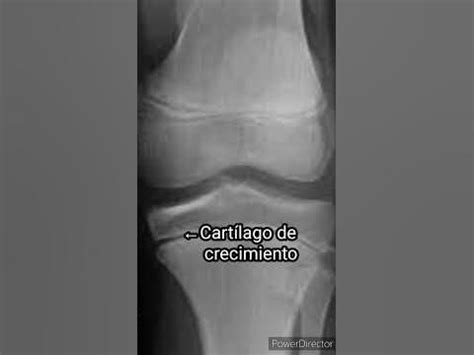

¿Cómo crecen los huesos? Los huesos de los niños y adolescentes son más pequeños que los de los adultos y contienen "zonas de crecimiento" llamadas cartílagos de crecimiento. Estos cartílagos están compuestos por células cartilaginosas que se multiplican, creciendo en longitud y convirtiéndose, más adelante, en hueso mineralizado y duro. Estos cartílagos de crecimiento son fáciles de detectar en una radiografía. Puesto que las niñas maduran antes que los niños, sus cartílagos de crecimiento se transforman en hueso duro a edades más tempranas. La construcción ósea se prolonga durante toda la vida, ya que el cuerpo renueva y reconstruye constantemente el tejido vivo de los huesos.